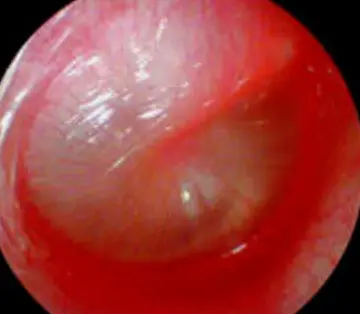

Acute otitis media

|---|---|---|

| Conductive Hearing Loss | Problem conducting sound waves anywhere along the route through the outer ear, tympanic membrane (eardrum), or middle ear (ossicles). | - Acute Otitis Media (AOM) - Otitis Media with Effusion (Glue ear) - Impacted Cerumen (Earwax) - Foreign body in canal - Perforated tympanic membrane - Otosclerosis - Microtia/Atresia of the ear canal |

| Sensorineural Hearing Loss (SNHL) | Damage to the inner ear (cochlea) or to the nerve pathways from the inner ear to the brain (Cranial Nerve VIII). | - Congenital: CMV, Toxoplasmosis, Rubella (TORCH infections) - Genetic: Usher syndrome, Waardenburg syndrome - Acquired: Meningitis, Mumps, Ototoxic drugs (e.g., Gentamicin) - Noise-induced trauma - Perinatal hypoxia |

| Mixed Hearing Loss | A combination of conductive and sensorineural hearing loss (damage in both the outer/middle ear and the inner ear/nerve). | - Chronic Suppurative Otitis Media (causing both ossicular damage and toxic effects on the cochlea) - Temporal bone fractures - Certain congenital malformations - Otosclerosis involving the cochlea |